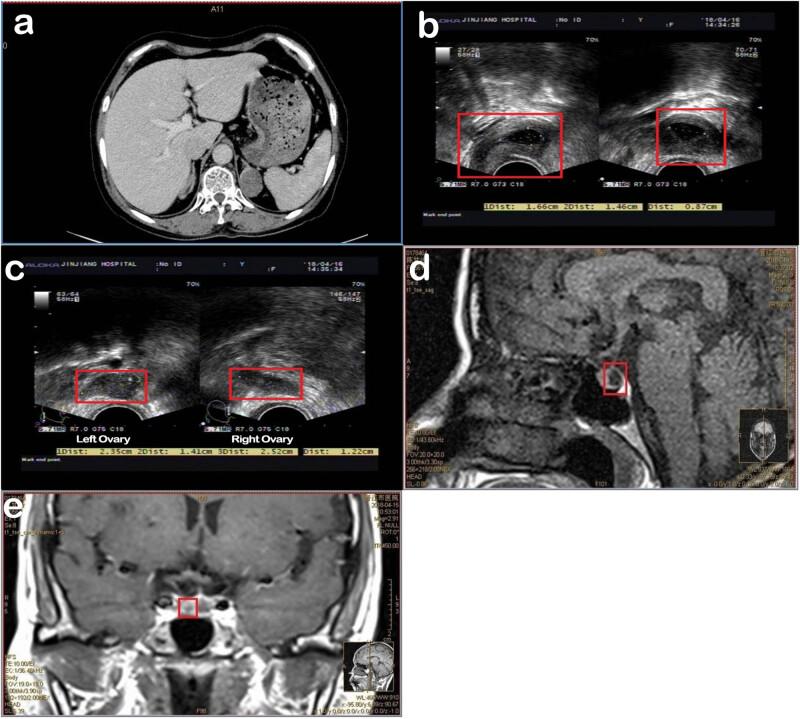

The present study reports a patient case with a 17α-hydroxylase deficiency accompanied by triple X syndrome. A 17α-hydroxylase deficiency leads to a very low 17α-hydroxylated steroid synthesis as well as a non-feedback increase in the adrenocorticotropic hormone level. Meanwhile, the progesterone level increases the 17α-hydroxyprogesterone level and decreases the dehydroepiandrosterone sulfate level. The patient is characterized by intractable hypokalemia, high urinary potassium, hyperaldosteronemia, hyporeninemia, hypocortisolemia, hypertension, gonadal and secondary sexual dysplasia, a decreased estrogen level, primary amenorrhea, and infertility. The imaging findings indicate a presence of multiple bilateral adrenal gland adenomas, and the sequencing indicates a missense CYP17A1-E7 gene pathogenic variant. The karyotype is a 47, XXX [3]/46, XX [47] low-level chimeric karyotype. The patient's parents are cousins. To our knowledge, this patient is the first case diagnosed with congenital adrenal hyperplasia caused by hydroxylase deficiency and triple X syndrome. The uniqueness of this case is that this patient has two very rare genetic diseases, probably due to the marriage of close relatives.

本研究报告了一例伴有三倍体X综合征的17α-羟化酶缺乏症患者病例。17α-羟化酶缺乏导致17α-羟化类固醇合成极低,同时促肾上腺皮质激素水平出现非反馈性升高。与此同时,孕酮水平升高,17α-羟孕酮水平升高,硫酸脱氢表雄酮水平降低。该患者的特征为顽固性低钾血症、高尿钾、醛固酮增多症、低肾素血症、低皮质醇血症、高血压、性腺及继发性性发育异常、雌激素水平降低、原发性闭经和不孕。影像学检查结果显示存在多个双侧肾上腺腺瘤,测序显示存在错义CYP17A1-E7基因致病变异。核型为47,XXX[3]/46,XX[47]低水平嵌合核型。患者的父母是近亲。据我们所知,该患者是首例诊断为先天性肾上腺增生症伴羟化酶缺乏和三倍体X综合征的病例。该病例的独特之处在于该患者患有两种非常罕见的遗传病,可能是由于近亲结婚所致。